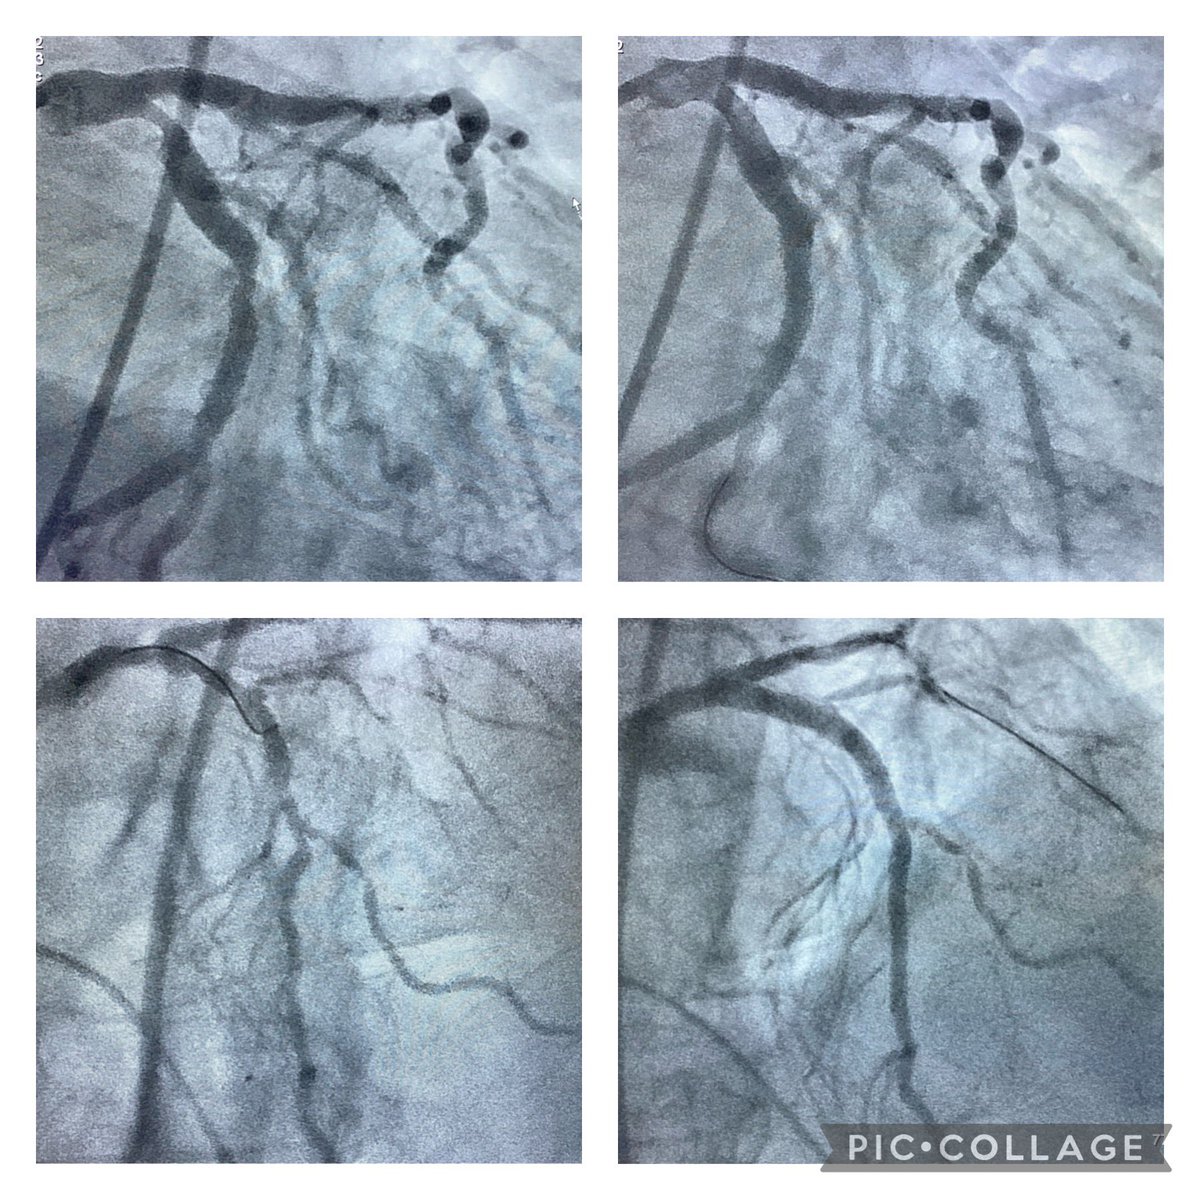

86yo man, CKD stage V, cardiac arrest during hemodialysis, cardiogenic shock stage C. No MCS due to severe PAD. Ostial cx pre-dilated with Wolverine 3.5x15. Ivus guided TAP with very short neo carina, well expanded stent despite severe calcification